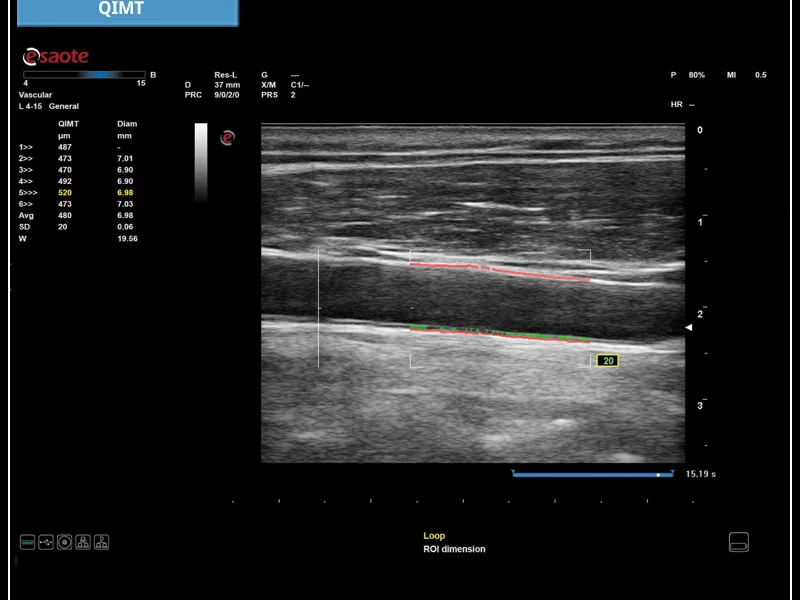

MyLab™X5 - QIMT

MyLab™X5 is equipped with comprehensive cardiac and vascular configurations. It functions as a complete system for ultrasound cardiovascular examination, and features customizable measurements and reporting.